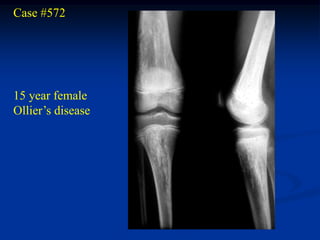

Case #572

15 year female

Ollier’s disease

AP close up knee

Forearm disease